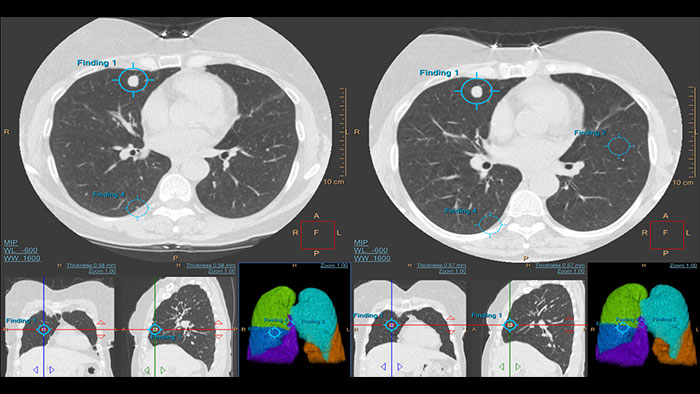

Assessing lung nodules over time

Enables review and analysis of thoracic CT images, providing segmentation, quantification and characterization of physician-indicated lung nodules. The application can be used in both diagnostic and screening evaluations, supporting Low Dose CT Lung Cancer Screening*

Automated computer aid for lung nodule detection

Artificial second reader to support the detection of lesions or nodules which may have been missed. It offers an automated process that identifies and marks regions of interest based on image features associated with lung nodules. It is intended for use as a second reader after an initial interpretation of the diagnostic image has been performed.